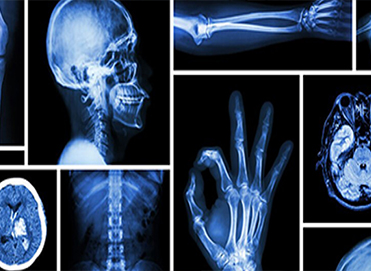

A 32-slice CT scan uses advanced technology to produce high-quality, detailed cross-sectional images of the body using X-rays. It allows for a greater number of images (32) to be captured per rotation of the scanner, which can result in faster scan times and potentially lower radiation exposure compared to older CT scan models.

Detailed images: The ability to acquire 32 images per rotation allows for more detailed images of internal organs, bones, and tissues. Faster scan times: The enhanced image acquisition process can lead to shorter scan times, potentially reducing patient anxiety and discomfort. Lower radiation exposure: With modern technology and protocols, 32-slice CT scans can often provide the same level of detail with lower radiation exposure compared to older models.

32-slice CT Scan

Believe Hospital 32-slice CT scan service offers advanced diagnostic imaging.

Radiology

At Believe Hospital Radiology Department, advanced imaging technology and compassionate care combine to ensure accurate diagnoses and patient comfort.